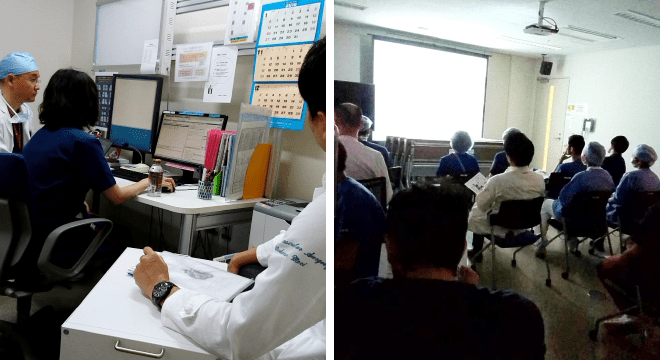

安心のチーム体制

診療科の枠を超えた「ハートチーム」がサポート東部病院では、「ハートチーム」を結成し、2012年末から始動しています。担当医が所属する診療科の治療法を優先するのではなく、診療科の垣根を越え、医師やスタッフ同士が話し合い、それぞれの患者さんに合った最適な治療法を提案します。治療後も、継続してハートチームがサポートします。

ハートチームカンファレンス

ハートチームカンファレンス問診や検査結果をもとに、循環器内科(カテーテル治療医、心エコー医)、心臓血管外科ほか、各部門の専門家で構成されたハートチームで、患者さんに適した治療の選択を行うべく話し合いを行います。